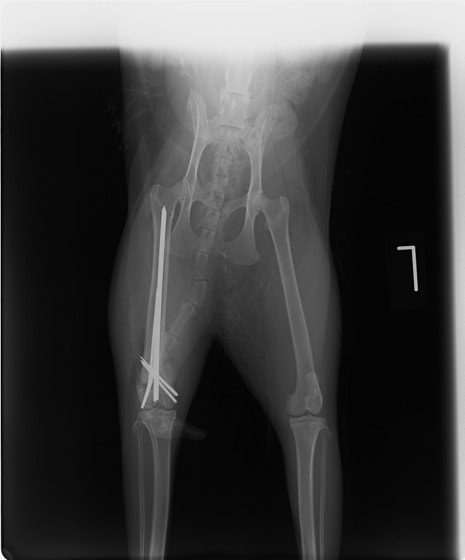

症例3:キルシュナーワイヤーのピンニングによる整復

ペルシャ猫 11ヶ月齢 雄

他院にて左大腿骨遠位の成長板骨折(salter-harrisⅠ型)が認められており、治療相談を目的として来院。当院にて、キルシュナーワイヤーを用いたピンニングにより骨折部位の整復を行いました。術後の経過は良好で、現在も経過観察中です。

術前レントゲン

術後レントゲン

Arthrex社のターゲティングデバイスを用いてピンニングの位置を調整することで、確実な固定を行っています。当院ではこの手術器具以外にも、人の手術にも使用される様々な器具を導入し、手術精度を高め、また医療メーカーと新しい器具の開発、試作にも取り組んでおります。